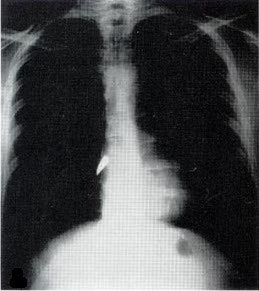

X-rays, a type of electromagnetic radiation, had been discovered in 1895 by Curie’s fellow Nobel laureate, Wilhelm Roentgen. As I describe in my book Strange Glow: The Story of Radiation, almost immediately after their discovery, physicians began using x-rays to image patients' bones and find foreign objects -- like bullets.

But at the start of the war, x-ray machines were still found only in city hospitals, far from the battlefields where wounded troops were being treated. Curie's solution was to invent the first "radiological car" -- a vehicle containing an x-ray machine and photographic darkroom equipment -- which could be driven right up to the battlefield where army surgeons could use x-rays to guide their surgeries.